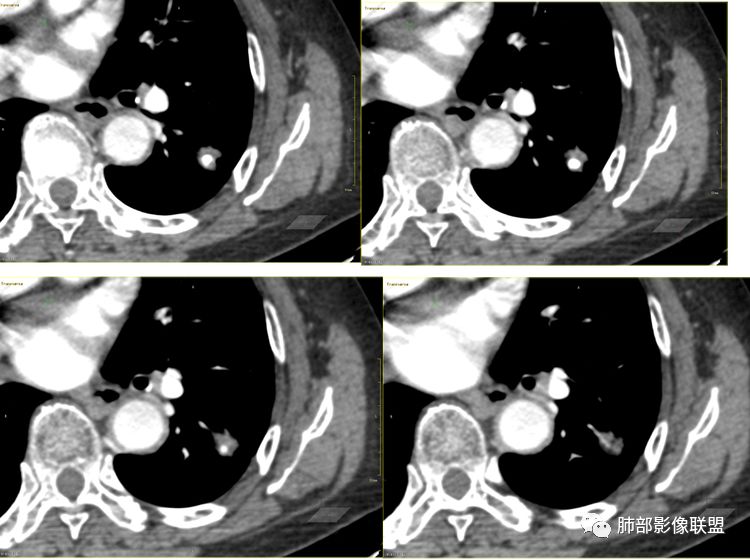

看了薄层我也倾向于恶性肿瘤。叶间裂牵拉比较明显了,分叶,胸膜凹陷,周围清晰磨玻璃,支气管也闭了。

这属于瘢痕癌,有炎性特点,有长索条影,有钙化,血管进入,比较自如,边缘似乎有点毛糙,有长索条影,有恶性特点,大家都关注钙化了,关注边缘收缩了,

南边:这类病变,其实我们读了很多了。属于什么样的病变,属于瘢痕癌。我先标注给大家看一下,这个良恶性特点在哪里:

南边:首先,他有炎性的特点,有长索条吧,还有一个大的钙化。对不对,血管进去里面走行也自如,边缘似乎有点毛糙,但是没有薄层,不是很好看。

南边:它符合一个纤维索条影的一些病变存在的特点,为什么,有长索条边缘是吧,近端也是。

南边:你看看这个主体层面,大的一些层面,看看纵隔窗跟肺窗一对比,就发现病变不密实,似乎缩小了一大半,这就不正常了。

特别是在这种有瘢痕的基础上是吧,这个瘢痕很明显。南边:

以往有专家总结这个体积缩小超过一半的,一般会考虑炎性病变,为什么,它渗出为主的吧,但是我们后面的后来就发现这个老前辈总结出来的理论有很多东西,就不合适。磨玻璃影的边界,这个边界如何?清不清楚,这个很重要,如果边界是很模糊的,不用考虑那是炎症。那你像这种边界非常清楚的又不密实的,那种高度警惕恶性的。